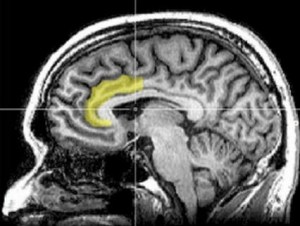

Les personnes dépendantes traitent les messages différemment : Dans cette étude, les participants ont pris part à un jeu virtuel, l’Iowa Gambling Task, souvent utilisé dans les études psychologiques sur la prise de décision. 4 jeux de cartes apparaissent sur un écran, et les participants sont informés qu’ils vont gagner ou perdre de l’argent en choisissant certains jeux. Les participants dépendants montrent moins d’activité cérébrale en réponse au message négatif qu’un type de jeu va les conduire à perdre. Les messages négatifs entraînent dans ce groupe des décisions beaucoup plus risquées. Les résultats suggèrent, pour les chercheurs, un niveau d’activité cérébrale dans les régions du cerveau qui permettent d’évaluer le risque bien plus faible chez les personnes dépendantes. Une région en particulier, le cortex cingulaire antérieur (Visuel IRM ci-contre), déjà impliquée dans une variété de troubles cliniques comme le TDAH, l’autisme, la schizophrénie et les troubles obsessionnels compulsif, est fortement impliquée par cette baisse d’activité. En fait, les 2 groupes traitent les messages différemment, notamment les messages qui soulignent une perte ou un risque. Cette ajoute aux données sur l’impact de différents types de messages sur les mécanismes neuronaux impliqués dans la prise de décisions risquées.

Source: Psychology of Addictive Behaviors Nov 12 , 2012 DOI: 10.1037/a0030633 Decisions During Negatively Framed Messages Yield Smaller Risk-Aversion-Related Brain Activation in Substance-Dependent Individuals (Visuel NIDA-NIH Credit: Geoff B. Hall/Wikimedia Commons)